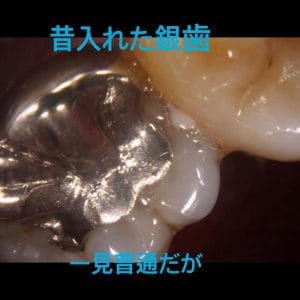

全ての銀歯の中に虫歯があるわけではありませんが、以下の理由から虫歯には注意が必要です。

1.銀歯はかけたり割れたりすることは絶対にないが、力がかかると”たわむ”

→ゆえに汚れが隙間に入りやすい

2.接着剤がつきやすいので、取れずらい

→ゆえに汚れもつきやすい

全ての銀歯の中に虫歯があるわけではありませんが、以下の理由から虫歯には注意が必要です。

1.銀歯はかけたり割れたりすることは絶対にないが、力がかかると”たわむ”

→ゆえに汚れが隙間に入りやすい

2.接着剤がつきやすいので、取れずらい

→ゆえに汚れもつきやすい

この症例のように、自覚症状が無くても銀歯を外してみたら大きな虫歯があるというケースも少なくありません。